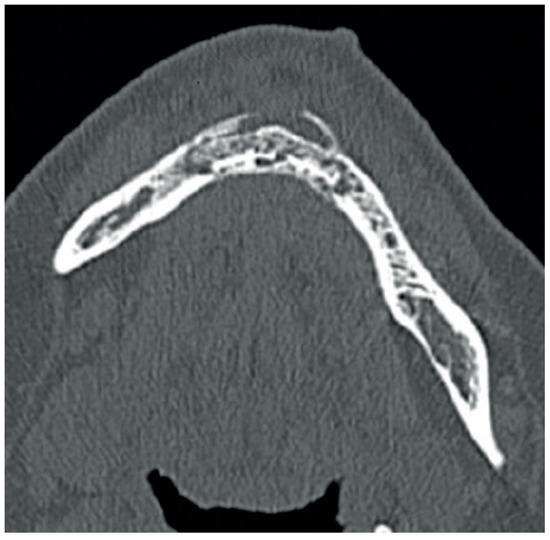

2.4. Diagnostic Assessment

2.5. Therapeutic Intervention